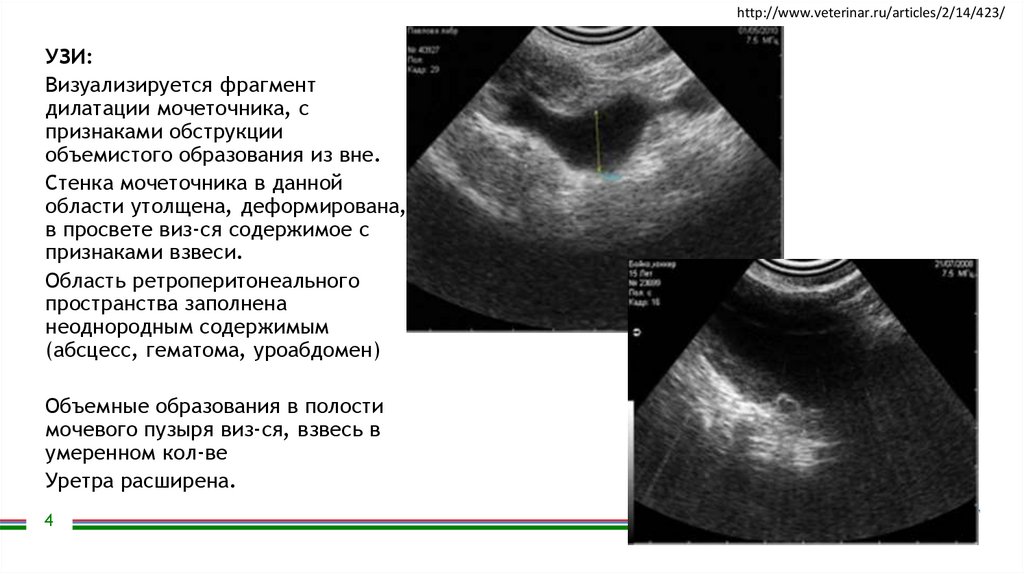

УЗИ:

Визуализируется фрагмент

дилатации мочеточника, с

признаками обструкции

объемистого образования из вне.

Стенка мочеточника в данной

области утолщена, деформирована,

в просвете виз-ся содержимое с

признаками взвеси.

Область ретроперитонеального

пространства заполнена

неоднородным содержимым

(абсцесс, гематома, уроабдомен)

Объемные образования в полости

мочевого пузыря виз-ся, взвесь в

умеренном кол-ве

Уретра расширена.